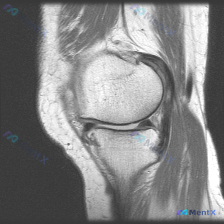

病例基础信息 这是一份特殊的膝关节影像评估需求:输入描述提示存在软骨异常 (Chondral abnormality),提供1张膝关节矢状位MRI静态图像,我们先看影像学分析结果: 影像学观察结果 1. 骨骼与软骨:股骨远端、胫骨近端、髌骨骨皮质完整,无骨折,无骨髓水肿;股骨髁、胫骨平台、髌股关节面...

看到这张膝关节MRI读片的需求,问题是观察到「软骨异常」,我整理了一下完整的病例资料和分析思路,和大家分享讨论。 一、影像基本信息 这是一张膝关节矢状位T1加权MRI影像,图像对比度尚可,解剖结构清晰,无明显运动伪影,层面接近膝关节中间矢状面,完整显示股骨远端、髌骨、膝关节间隙及胫骨近端结构。 二、...